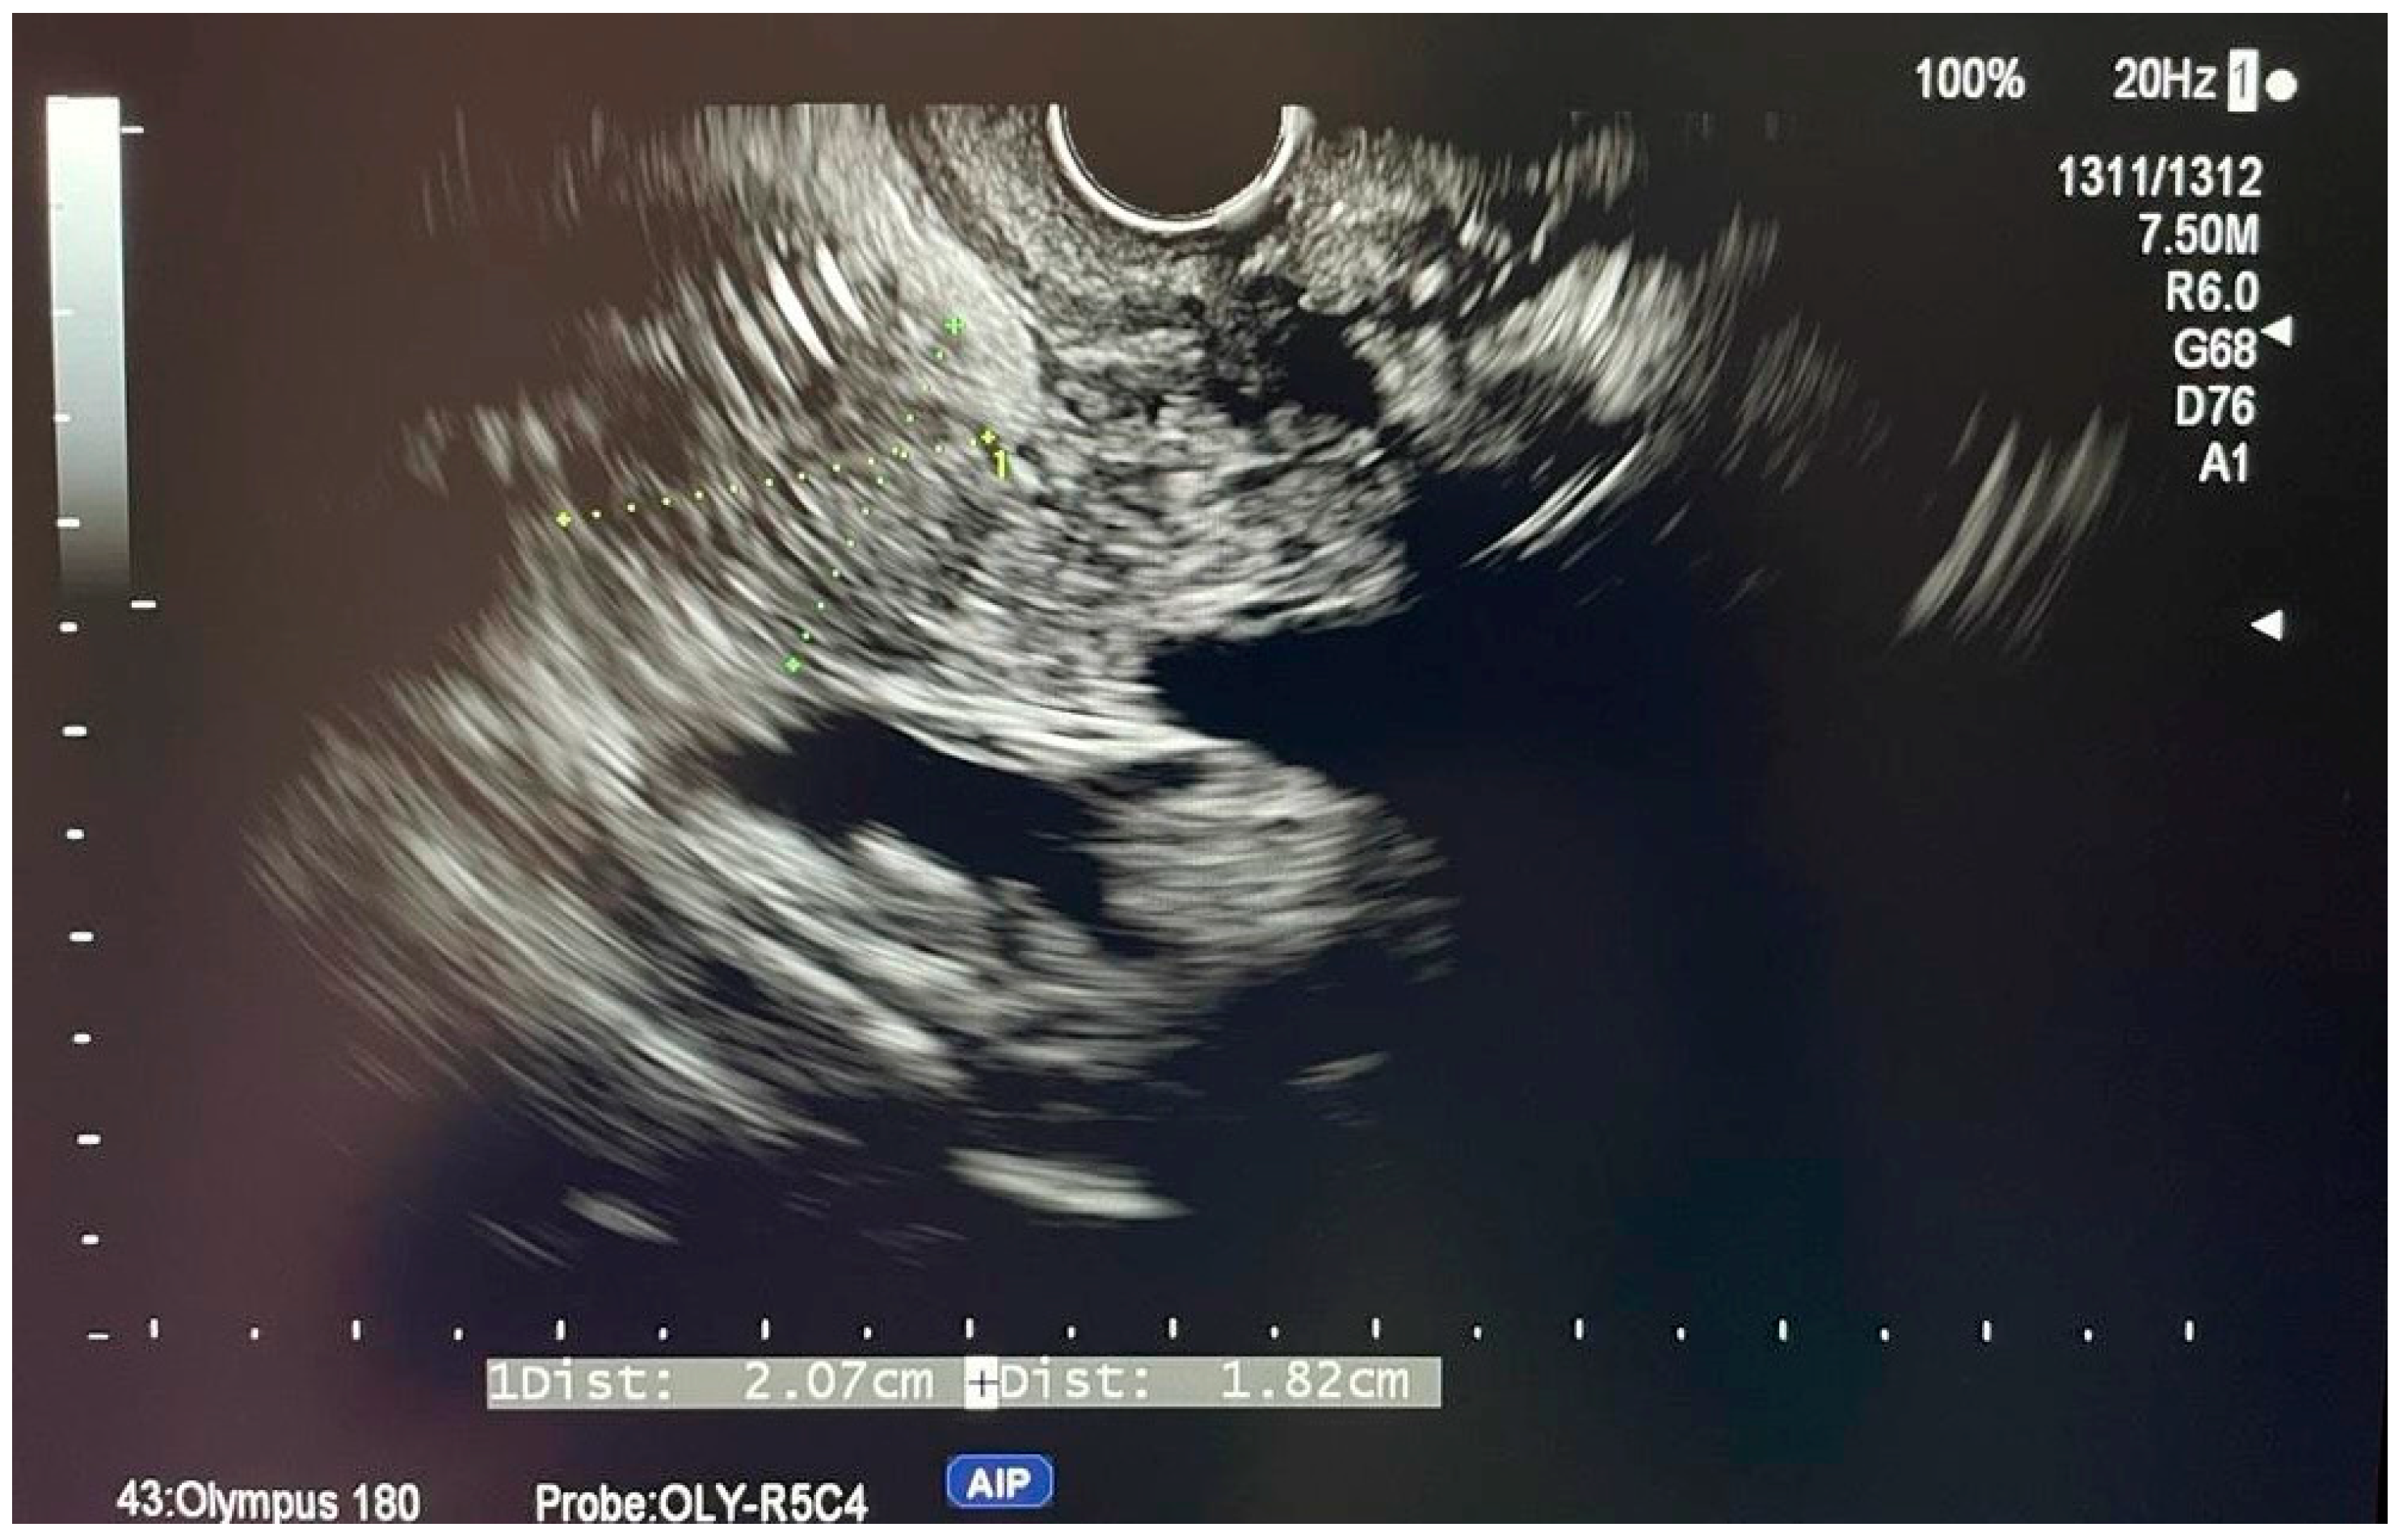

6.4.4. Intraductal Ultrasonography (IDUS)

- Chen, L.; Lu, Y.; Wu, J.-C.; Bie, L.; Xia, L.; Gong, B. Diagnostic Utility of Endoscopic Retrograde Cholangiography/Intraductal Ultrasound (ERC/IDUS) in Distinguishing Malignant from Benign Bile Duct Obstruction. Dig. Dis. Sci. 2016, 61, 610–617. [Google Scholar] [CrossRef]

- Tischendorf, J.J.W.; Meier, P.N.; Schneider, A.; Manns, M.P.; Krüger, M. Transpapillary intraductal ultrasound in the evaluation of dominant bile duct stenoses in patients with primary sclerosing cholangitis. Scand. J. Gastroenterol. 2007, 42, 1011–1017. [Google Scholar] [CrossRef]

- Menzel, J.; Poremba, C.; Dietl, K.H.; Domschke, W. Preoperative diagnosis of bile duct strictures—Comparison of intraductal ultrasonography with conventional endosonography. Scand. J. Gastroenterol. 2000, 35, 77–82. [Google Scholar]